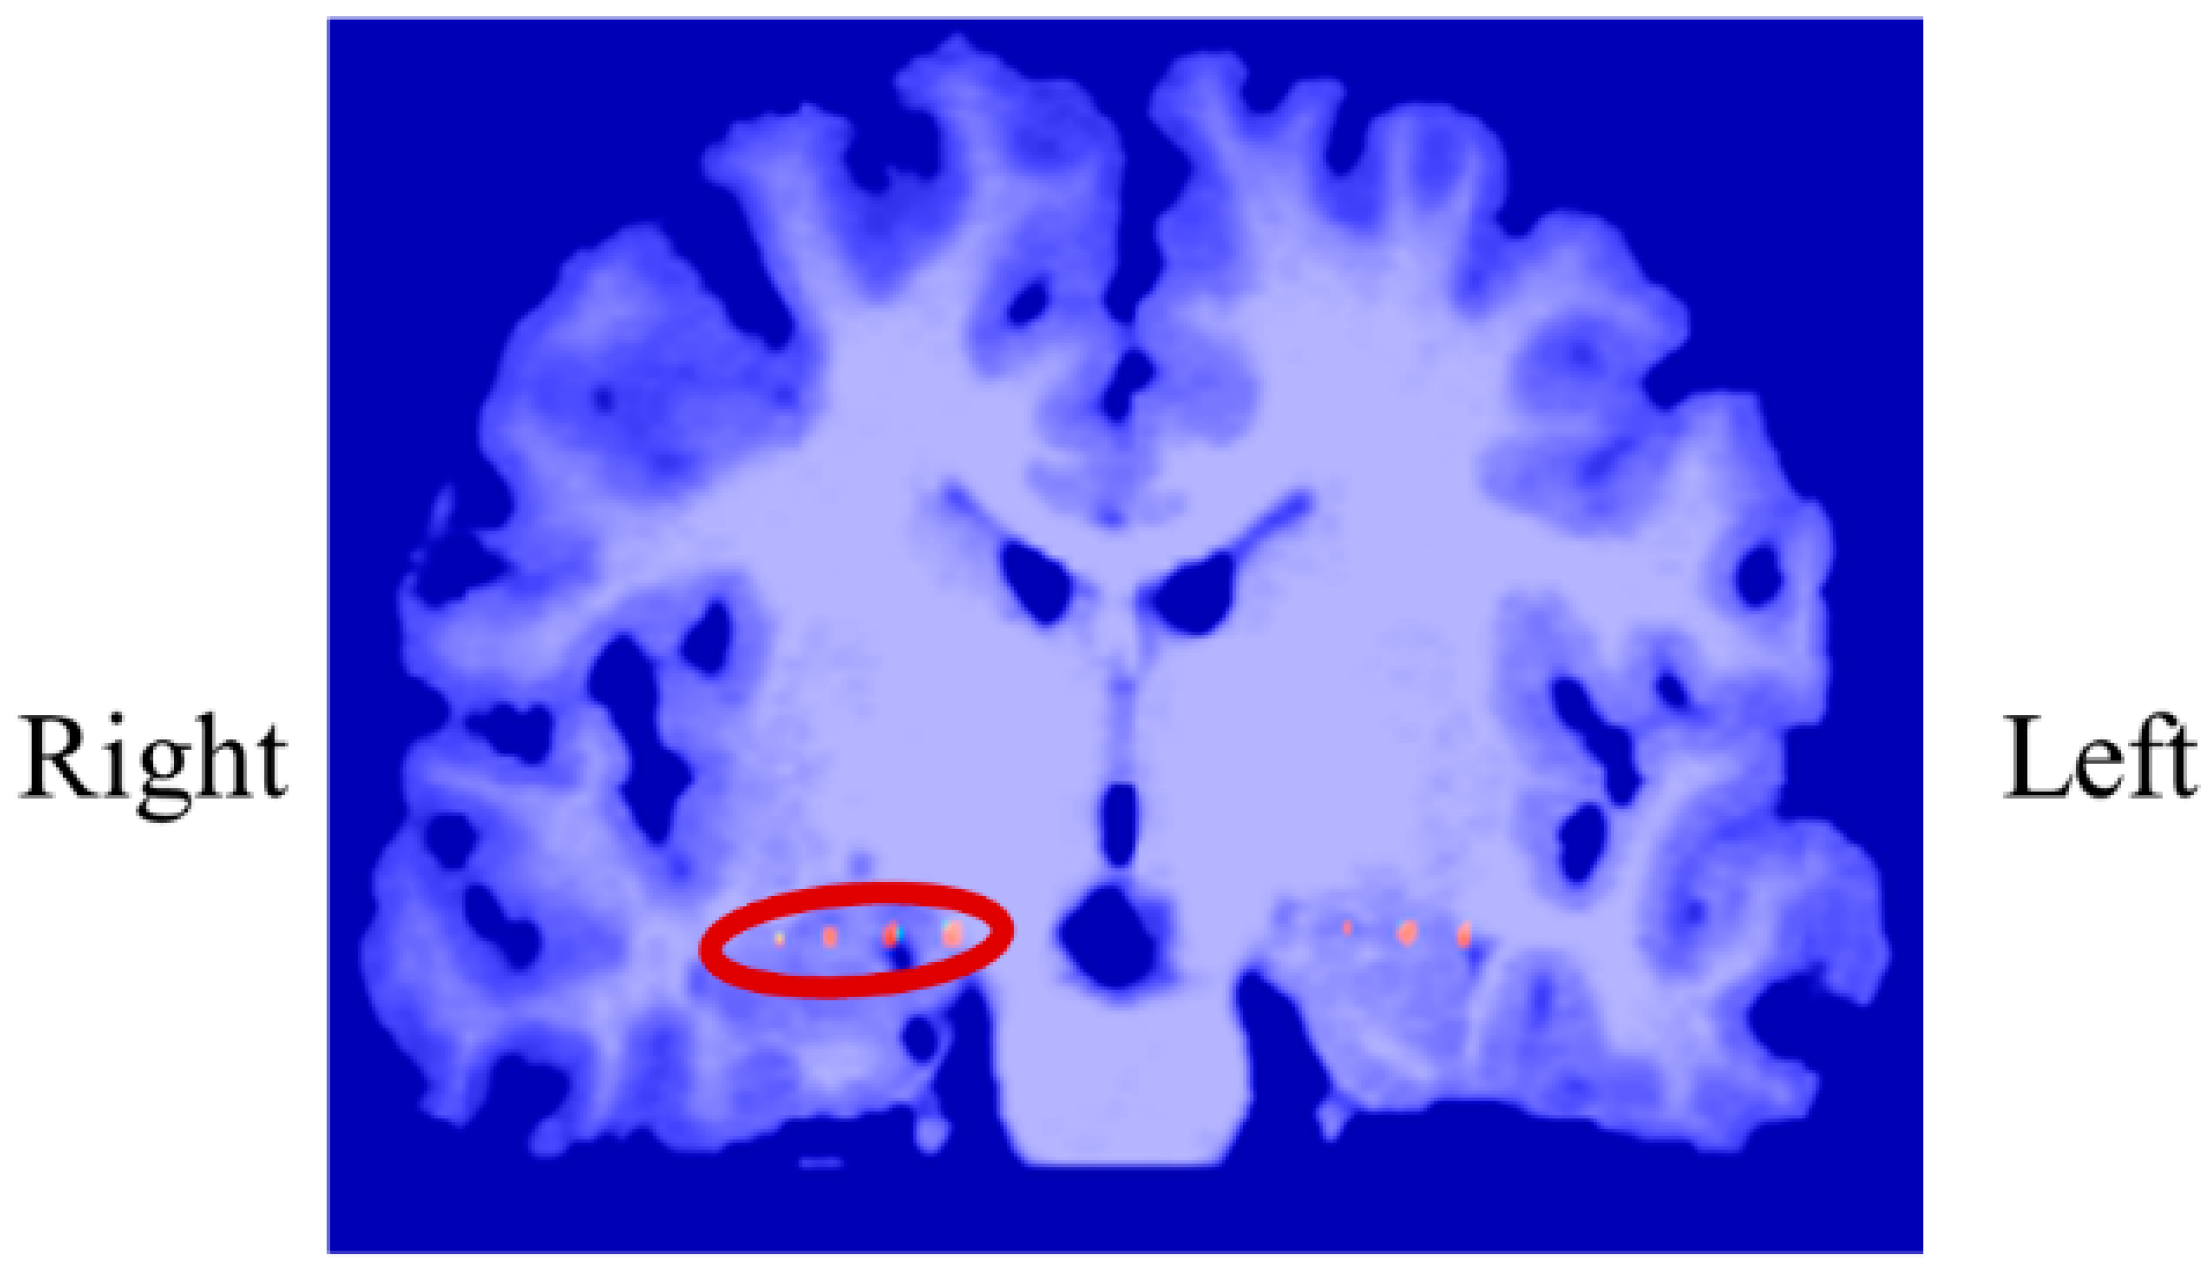

To investigate the causes of the differences in NF signal values and LTRi (Up < Down) in the first and intermediate sessions, we examined the within-session transitions in delta power and low theta power, as shown in Figure 28.